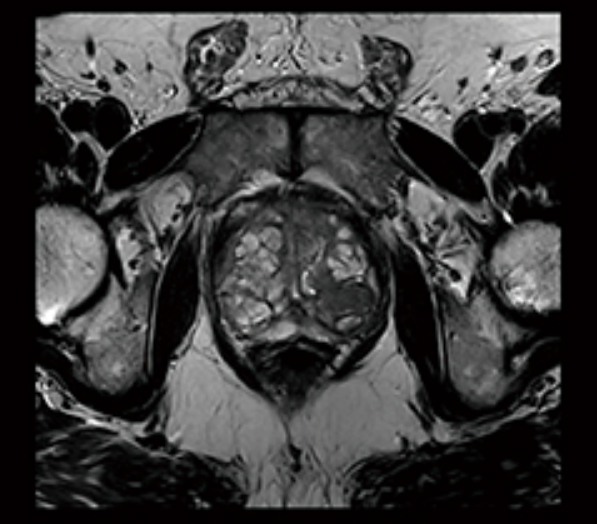

3Tの高い磁場強度とAIを用いて開発された最新のテクノロジーにより脳、脊椎などの微細病変、脳血管の小さい動脈瘤、全身各部位の高精細な画像検査を行うことができます。画像再構成プロセスにDeepLearning(深層学習) Reconstructionを用いたDeep Resolveは先進的なMR画像再構成技術です。撮像時間を短縮しても、従来と比較して高分解能な画像を得ることが可能になりました。また、呼吸停止ができない方でも、装置が自動的に呼吸情報を認識し、画像収集に反映されます。

- 脳神経領域や脊髄、関節、骨盤腔内の診断能に優れている